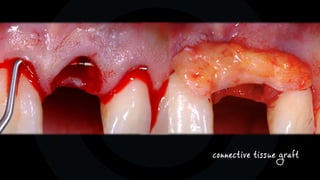

tunnel technique, (split thickness)

full thickness flap, dubbel-sling

sub-papilla sutures

connective tissue graft